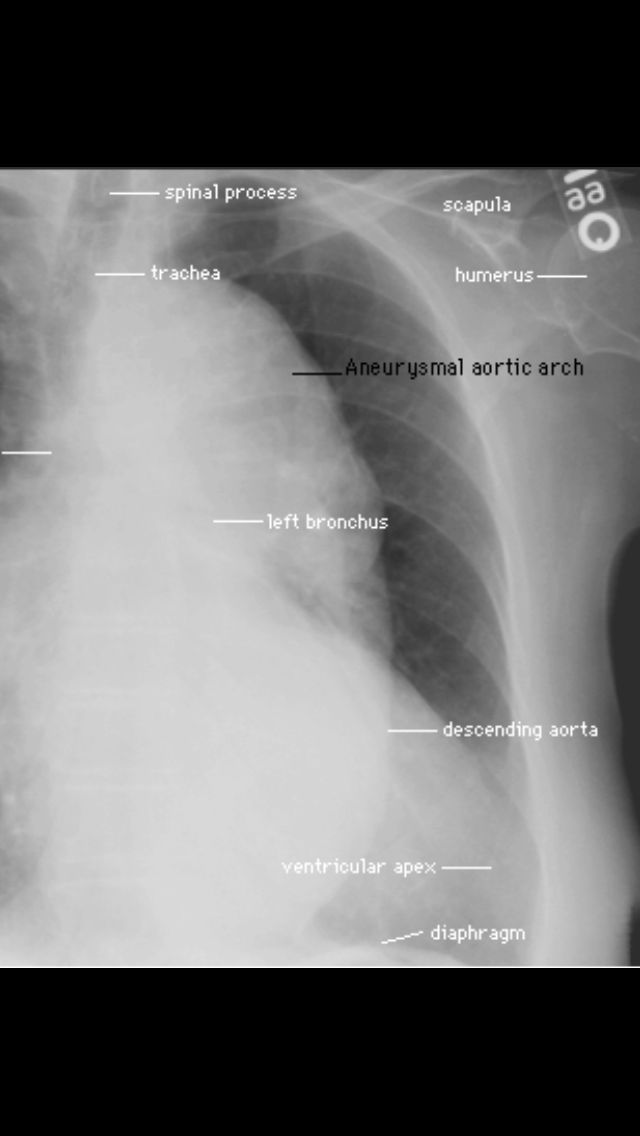

Chest X Ray Training . The tutorial also discusses anatomical structures that are not easily seen, but become visible when abnormal due to disease.

The tutorial also discusses anatomical structures that are not easily seen, but become visible when abnormal due to disease.